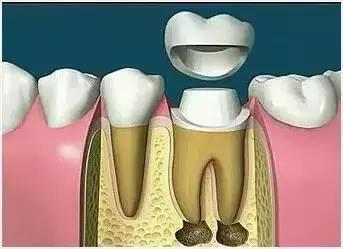

X光片显示根管充填完好,可进行暂时或永久牙体修复,带上牙冠,保护患牙。至此根管治疗才可算完成,同时根管治疗后还需复诊,一般周期可为3个月、半年、1年、2年或更长。